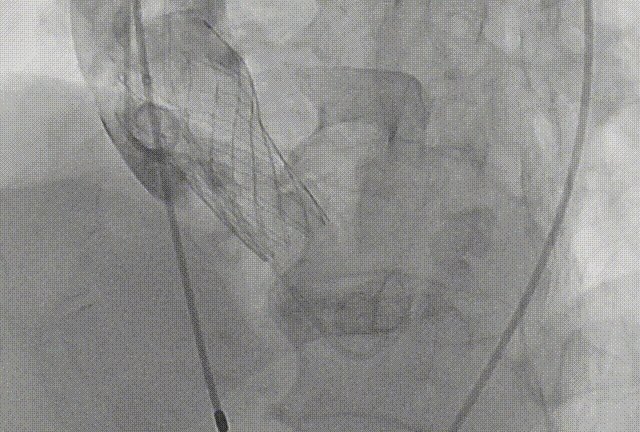

患者病史 术前超声提示:主动脉瓣退行性病变;中-重度狭窄并轻度返流;中-重度三尖瓣返流;中度肺高压 术前CT 三叶瓣,瓣叶增厚轻度钙化,右无交界有粘连,预计可以扩开,主动脉根部直径23.7mm,LVOT直径24.3mm,呈直筒型;双侧冠脉开口高度可,瓣叶长度小于冠脉开口上缘到主动脉根部的距离;窦部空间可,STJ、升主动脉内径可;主动脉水平夹角43.6°,非横位心;主动脉弓角、弓距可,左室内径可;外周入路无明显迂曲,有零星散状钙化,双侧股动脉内径可,均能通过20F大鞘,右股低分叉。 手术策略 推荐右侧股动脉为主入路使用20F大鞘,左侧股动脉为辅入路,右股分叉上方1cm穿刺;推荐使用22mm球囊预扩,预装AV26瓣膜,备AV29瓣膜,初始定位为真实瓣环上方3mm,瓣膜释放过程中释放张力使其自然下滑,工作位观察瓣膜稳定性,最终理想位置为零位;左右重合位:RAO23°CAU32°;右窦居中位:LAO5°CAU12°;左冠切线位:LAO34°CRA14°。 手术过程 术中右股动脉痉挛,内径变为3.8mm,遂更换左腋动脉入路;18球囊预扩,后植入AV26 ProStyle A®瓣膜;瓣膜精准释放于目标位置,超声显示无明显瓣周漏,血流动力学即刻改善。 术中右股动脉痉挛,内径变为3.8mm,更换左腋动脉 主动脉根部造影 18球囊预扩 初始定位 工作位观察 术后即刻表现:无瓣周漏,术后峰值压差10mmHg 术后3天复查超声峰值压差14mmHg Prostyle A®预装干瓣——助力临床最优化解决方案: 轻松过弓,精准可控:该病例经左腋动脉入路,输送系统较细的尺寸+柔顺的输送系统通过性能得到了很好的验证; 释放稳定:平衡的径向支撑力降低了释放过程中的张力,流入端小锥角设计能够迅速锚定贴边,80%可回收使得观察位和释放后的位置差距减少,大大提高了释放过程中的精准性,能够轻松应对高难度病例; 预装干瓣 便捷顺安:金仕生物专利抗钙化技术运用纳米技术去除组织内的细胞碎片和磷脂,封闭游离醛基,从根本上阻断了瓣膜钙化的多项因素,显著提升了瓣膜的耐久性;同时,相比较传统戊二醛保存方式,干式存储最大限度的保留心包的亲水亲油平衡,还原组织天然曲柔性,进一步保障了瓣叶开合,保证长期耐久性; 谢年谨教授 广东省人民医院 谢年谨教授指出:“对于外周血管条件较差的心脏瓣膜病患者,腋动脉路径凭借其更直接的解剖通路与更稳定的输送环境,为手术安全提供了重要保障,尤其适用于股动脉入路失败的复杂病例。该路径不仅能显著降低血管损伤、出血等并发症风险,还能通过更清晰的操作视野提升手术成功率;尤其在高龄、动脉硬化严重的患者群体中,腋动脉路径的适应性优势更为突出。 专家简介 荆志成 广东省人民医院 谢年谨 广东省人民医院 刘勇 广东省人民医院 · END ·